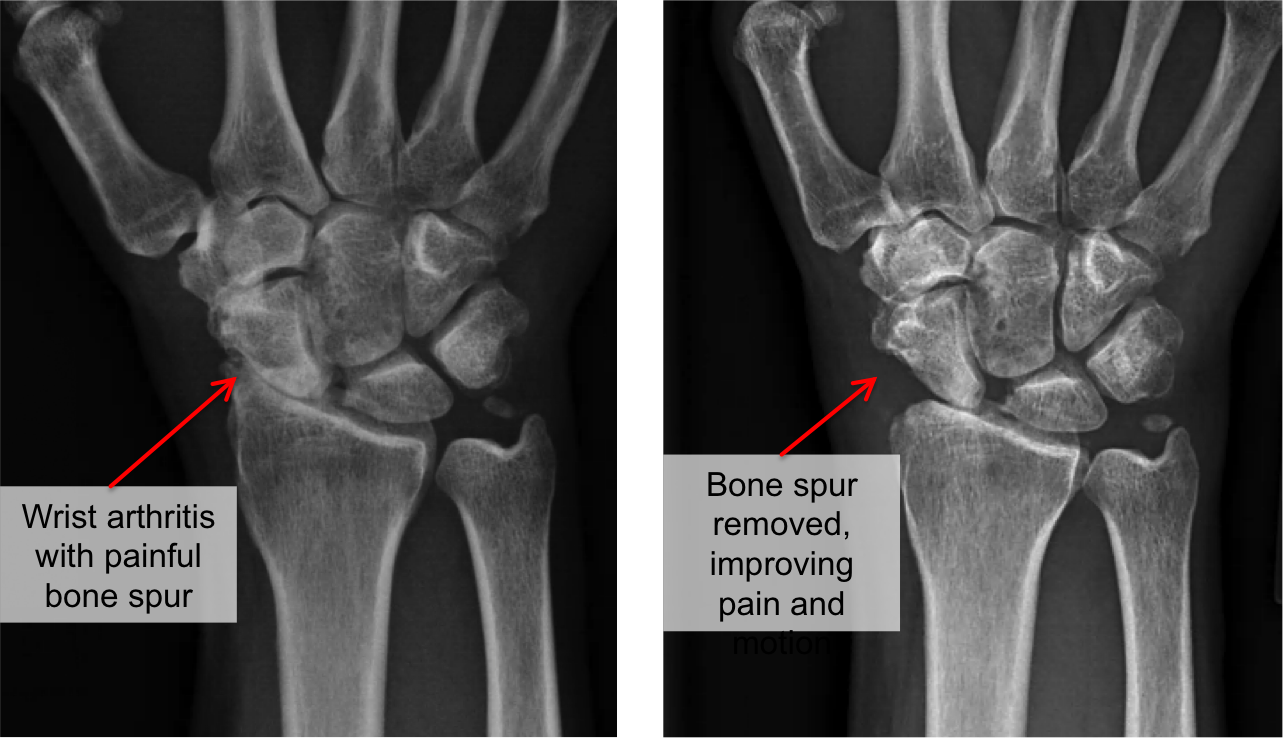

Wrist Arthritis Educational Guide Ladan Hajipour